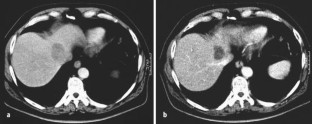

The present study retrospectively investigated survival, response and side effects after TACE of liver metastases in 21 patients with colorectal cancer and results are compared with previous literature. A total of 68 TACE procedures were performed. A suspension of degradable starch microspheres (DSM, Spherex®) and Mitomycin C was applied selectively into hepatic arteries via a transfemoral approach. DSM effect a temporary arterial occlusion. Follow-up studies were performed by contrast enhanced spiral computed tomography (CT).

Abb. 2a, b